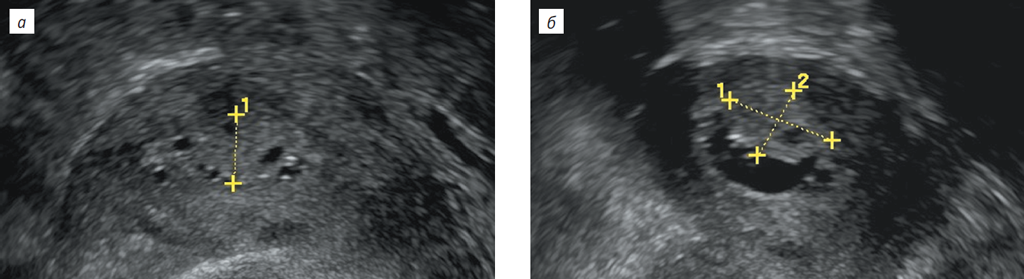

В сомнительных случаях у пациенток с увеличением толщины эндометрия перед решением вопроса о целесообразности гистероскопии и резектоскопии выполняют соногистероскопию для лучшей визуализации полости матки и повышения чувствительности УЗИ-методики (рис. 6) [54, 55].

Рис. 6. Пациентка Д., 67 лет. Прием тамоксифена 2 года 6 месяцев: а — при УЗИ толщина эндометрия 12 мм. Структура эндометрия — в виде пчелиных сот. В режиме ЦДК определяется одиночный сосуд; b — при соногистероскопии выявляется полип эндометрия по задней стенке полости матки, с кистозными включениями в структуре, на широком основании, размером 15 × 12 мм

Fig. 6. Patient D. aged 67 years, after 2 years 6 months of Tamoxifen therapy. Endometrial thickness = 12 mm. Endometrial tissue has a “honeycomb” appearance. A single vessel is visualized (color Doppler mapping) (a). A broad-based endometrial polyp with inclusion cysts, measuring 15 × 12 mm, is visualized along the posterior wall of the uterus (sonohysteroscopy) (b)